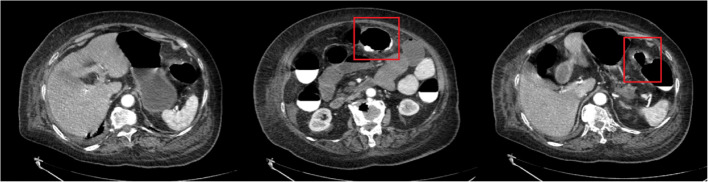

Case presentation: We present a clinically instructive case of a nonagenarian female initially diagnosed with colonic pneumatosis through imaging studies. Subsequent diagnostic reevaluation revealed progressive colonic necrosis requiring emergent surgical intervention. The patient underwent successful segmental colectomy with colostomy, achieving full recovery and discharge within 14 postoperative days.

Conclusion: This case highlights three critical aspects in managing geriatric patients with acute abdominal emergencies: The inherent diagnostic limitations posed by atypical presentations in elderly populations, including unreliable history-taking and attenuated physical signs; The insufficient sensitivity of conventional laboratory markers (leukocytosis, NEUT%, PCT, lactate elevation) for detecting intestinal ischemia; The pivotal role of contrast-enhanced computed tomography (CT) in surgical decision-making, particularly the prognostic significance of non-enhancing bowel wall dilatation as a radiographic hallmark of transmural necrosis. Early surgical consultation and protocolized CT interpretation are paramount for optimizing outcomes in this high-risk patient cohort.